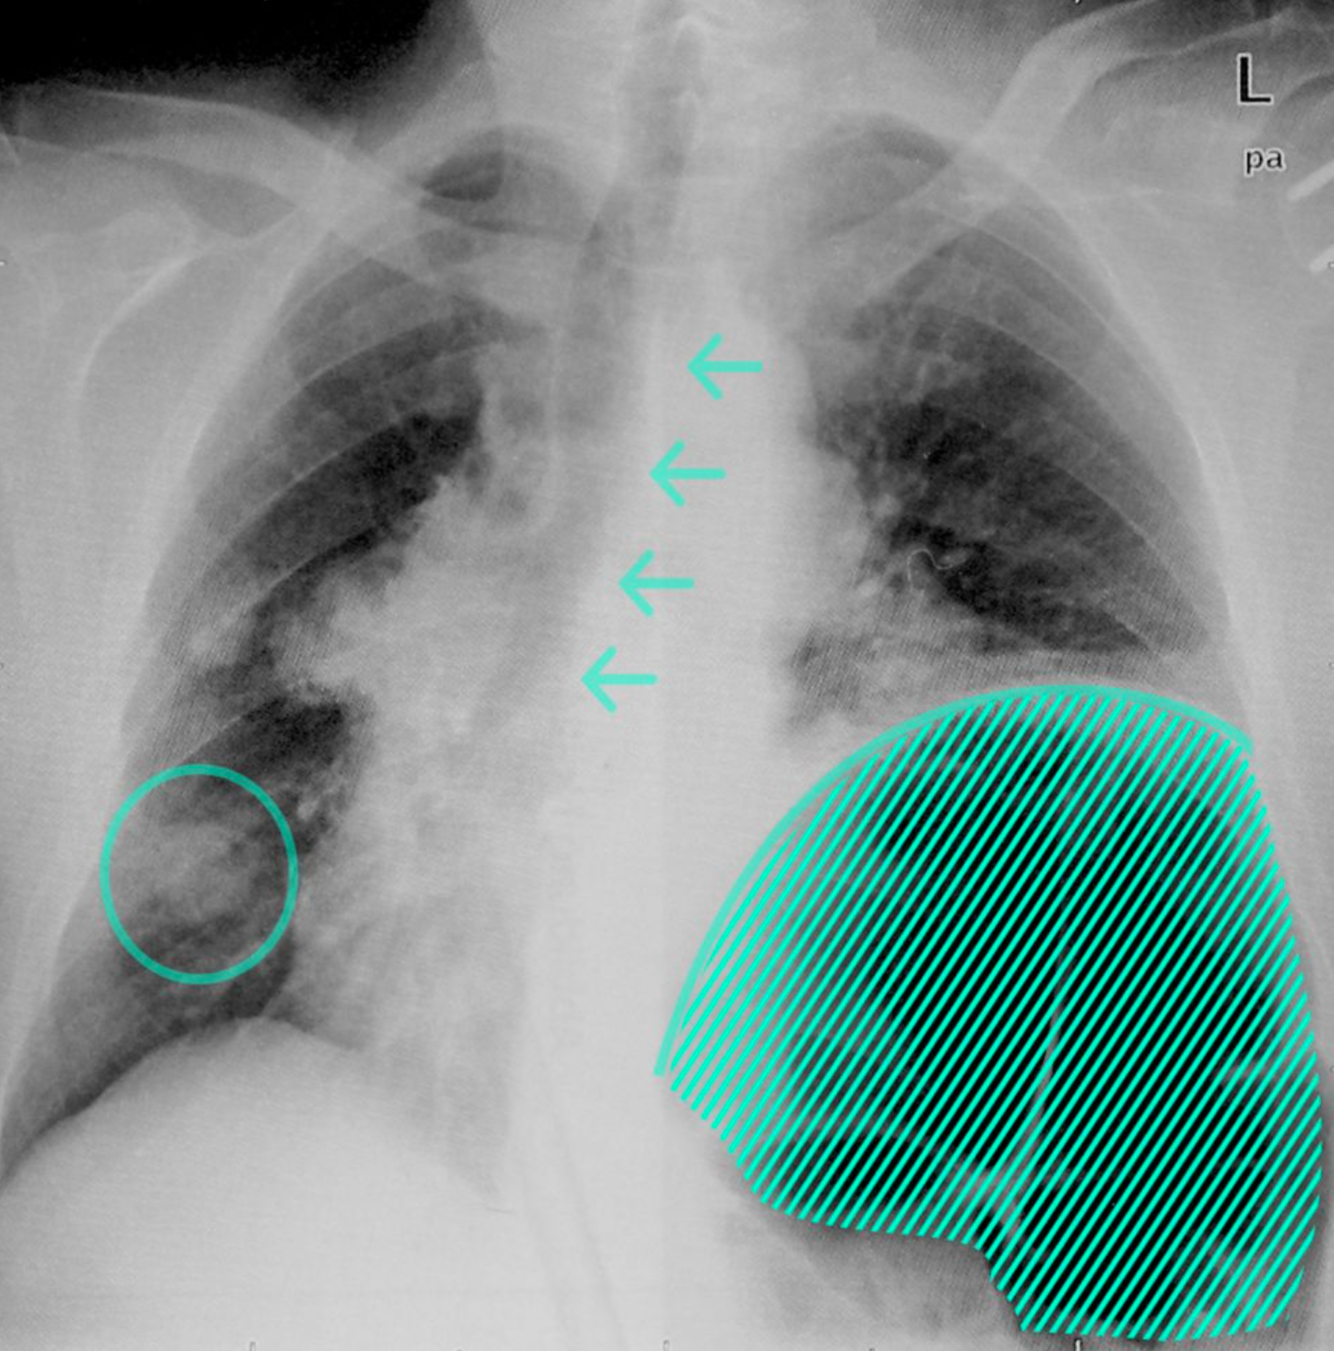

Elevation of the left hemidiaphragm with left basal atelectasis

There is basal atelectasis of the left lung with elevation of the left hemidiaphragm. The colon (hatched overlay) is filled with air and there is a mediastinal shift to the right (arrows). A round, possibly neoplastic lesion (circle) is visible in the lower zone of the right lung